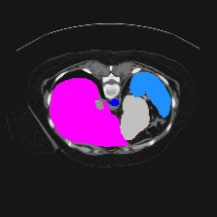

Transformers have made remarkable progress towards modeling long-range dependencies within the medical image analysis domain. However, current transformer-based models suffer from several disadvantages: (1) existing methods fail to capture the important features of the images due to the naive tokenization scheme; (2) the models suffer from information loss because they only consider single-scale feature representations; and (3) the segmentation label maps generated by the models are not accurate enough without considering rich semantic contexts and anatomical textures. In this work, we present CASTformer, a novel type of generative adversarial transformers, for 2D medical image segmentation. First, we take advantage of the pyramid structure to construct multi-scale representations and handle multi-scale variations. We then design a novel class-aware transformer module to better learn the discriminative regions of objects with semantic structures. Lastly, we utilize an adversarial training strategy that boosts segmentation accuracy and correspondingly allows a transformer-based discriminator to capture high-level semantically correlated contents and low-level anatomical features. Our experiments demonstrate that CASTformer dramatically outperforms previous state-of-the-art transformer-based approaches on three benchmarks, obtaining 2.54%-5.88% absolute improvements in Dice over previous models. Further qualitative experiments provide a more detailed picture of the model's inner workings, shed light on the challenges in improved transparency, and demonstrate that transfer learning can greatly improve performance and reduce the size of medical image datasets in training, making CASTformer a strong starting point for downstream medical image analysis tasks.